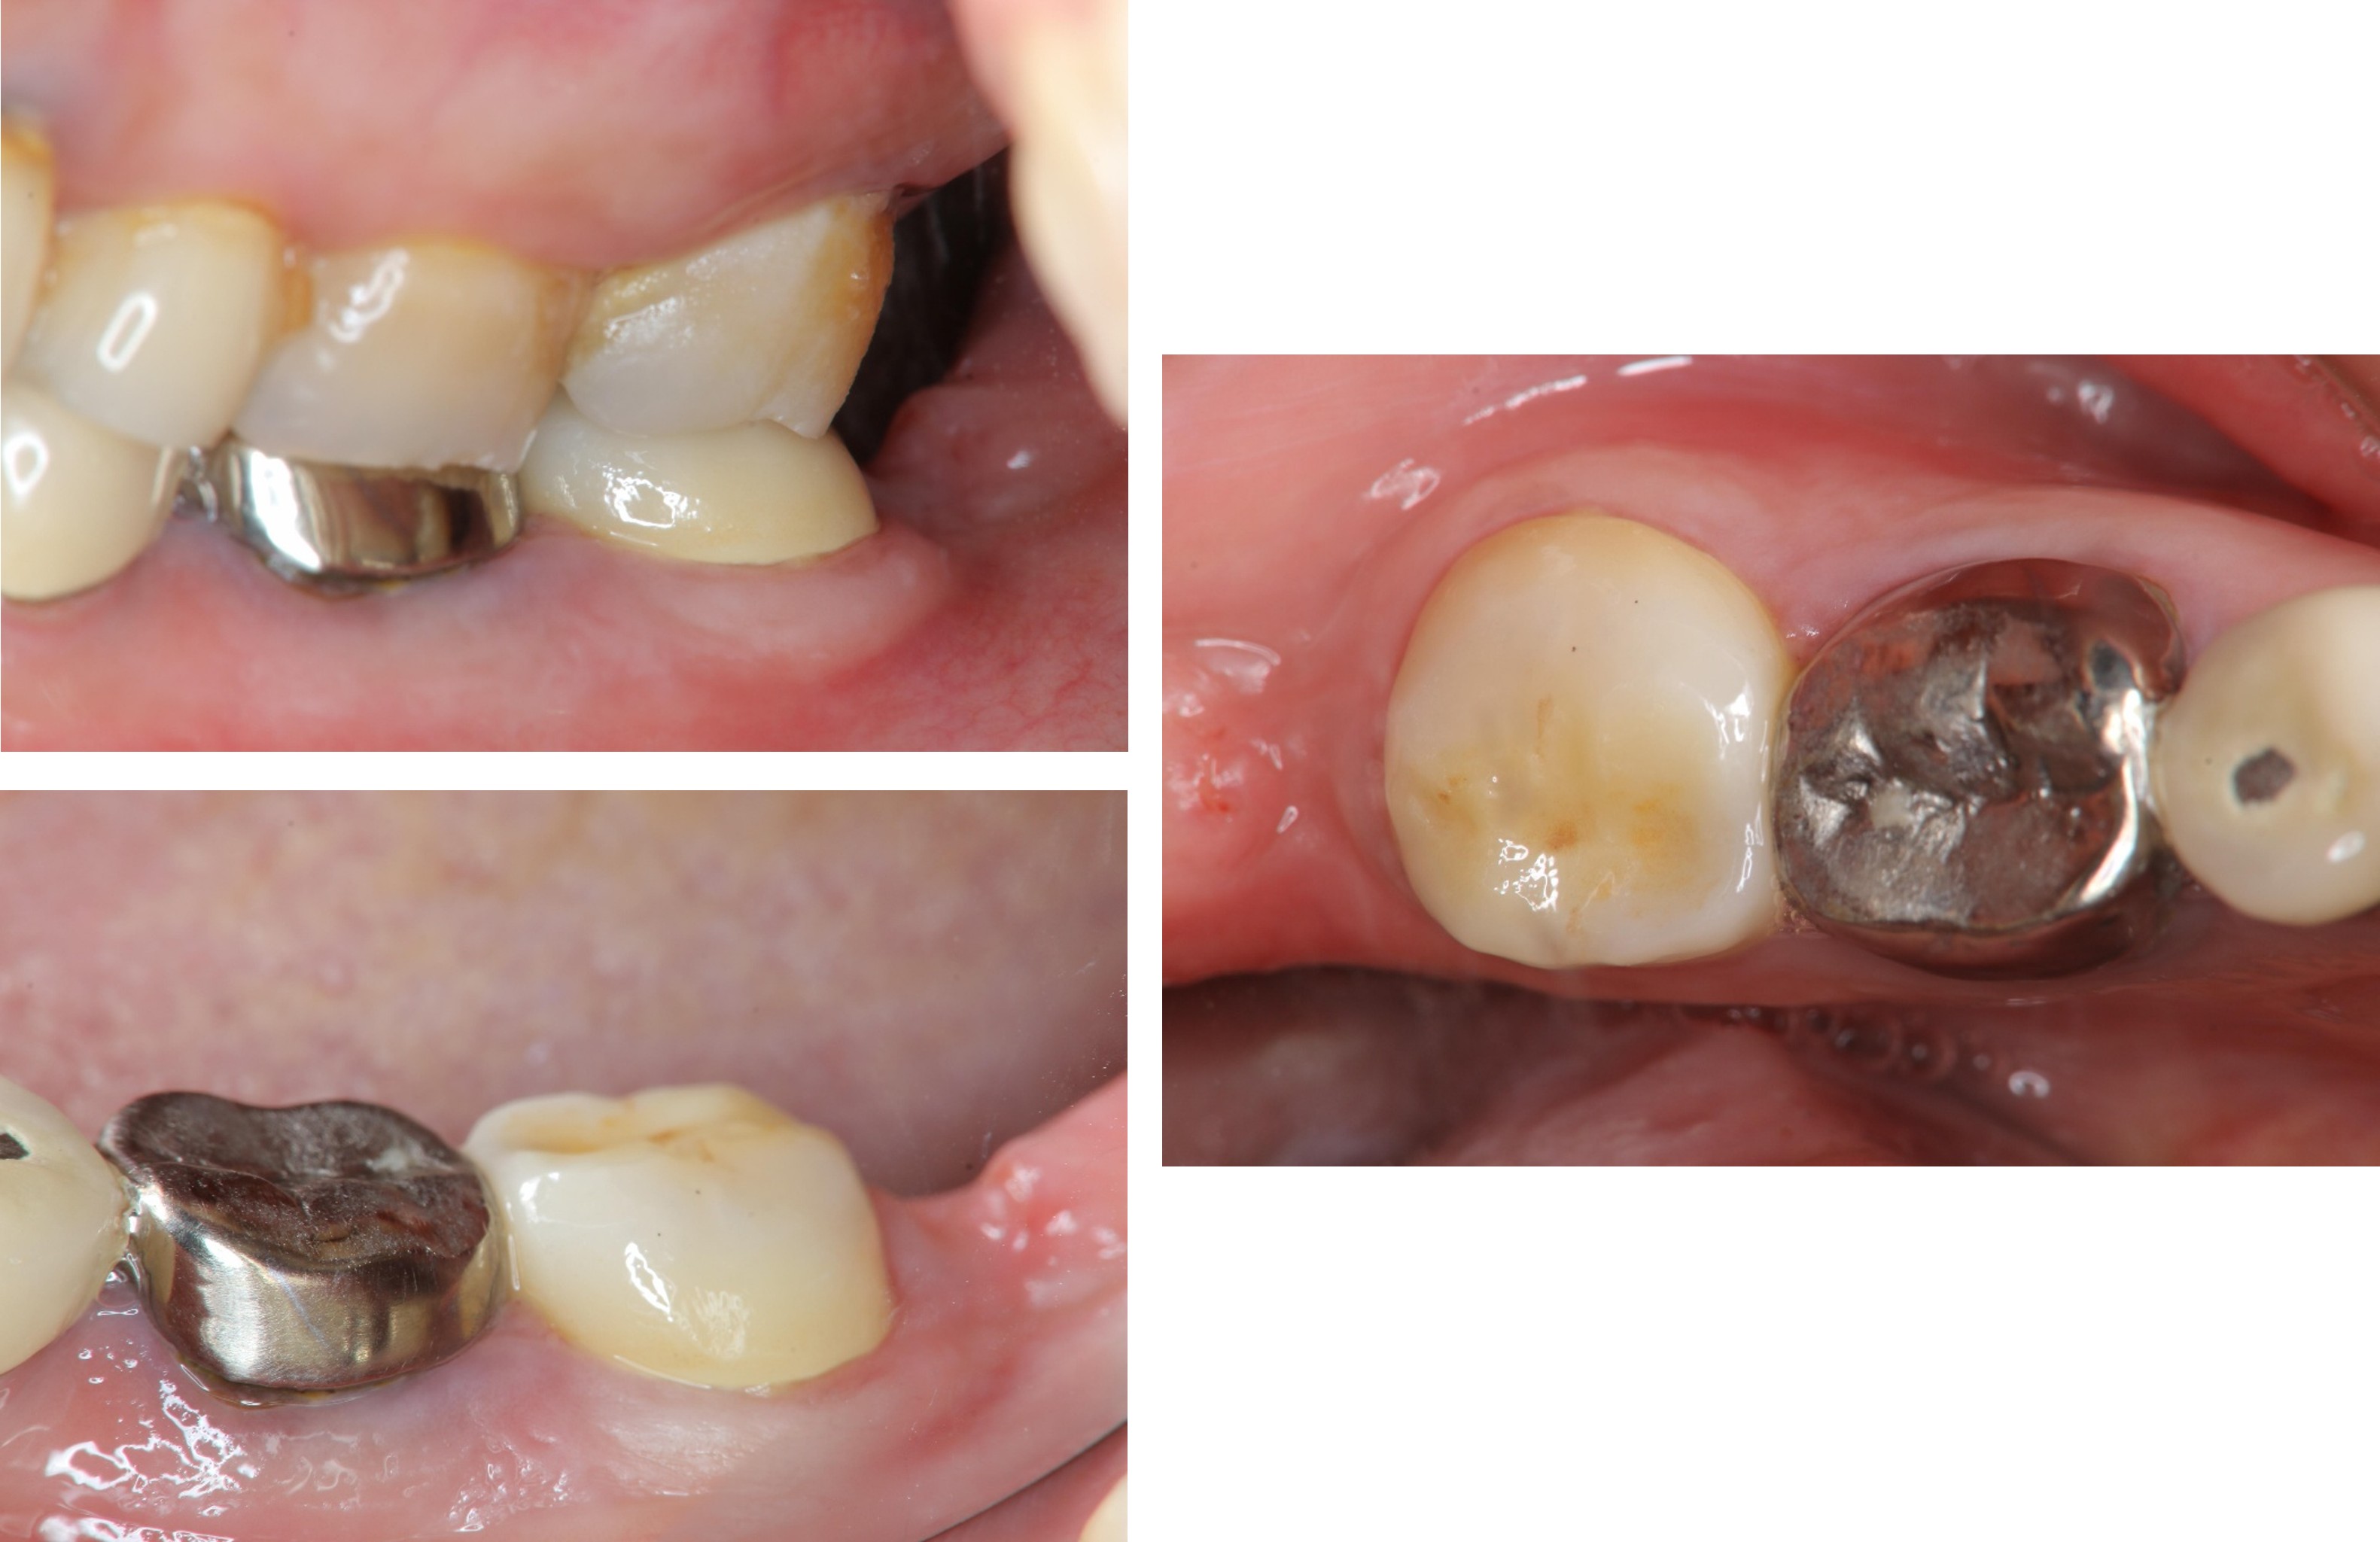

治療前,左下第二大臼齒蛀牙

膺復前評估牙齦、牙齒狀態

照相比色

治療後,牙周咬合良好

治療後,密合度良好

術前、術後比較